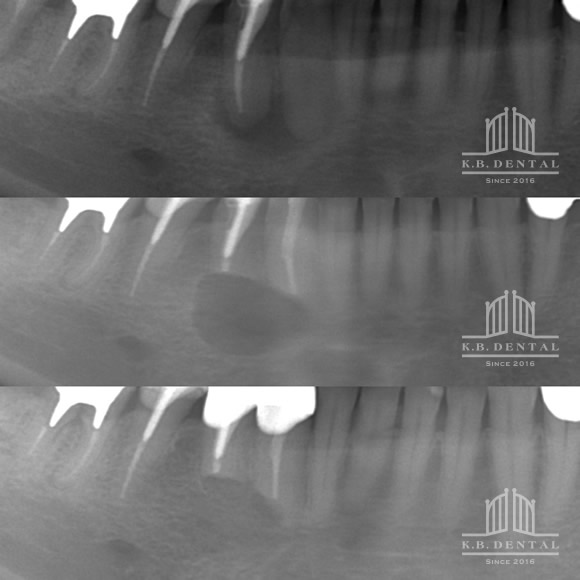

術後2年経過の最も典型的なエナメル上皮種です。再発率が非常に高いので最低でも5年以上の経過観察が必要となります。今回は摘出術と一部健常域まで辺縁切除(骨を削る)を行いました。

1枚目(パノラマ)上:術前 下:術後 摘出部分に新生骨を認めます。

2枚目(CT)上:術前 下:術後 摘出部分に新生骨を認めます。